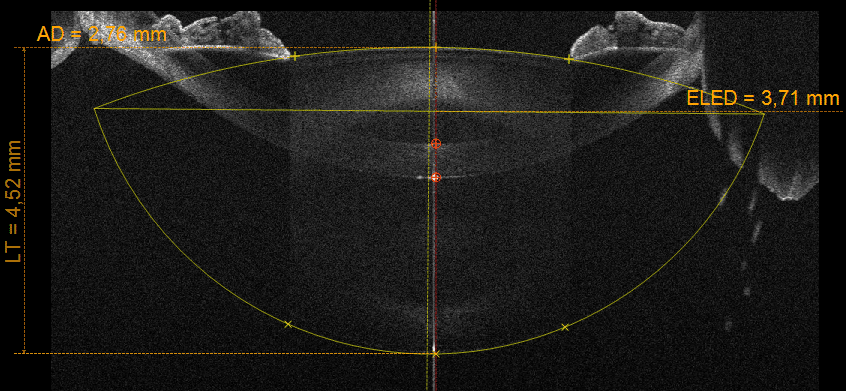

CORNEAL SECTION

The sharpness of the high-resolution section images on a diameter of 16 mm, together with the many details of the structure and the cornea layers brought to light by the instrument, are the most extraordinary features and appreciated by the specialists of the anterior segment (corneal and epithelial) . The device provides pachymetry, elevation, curvature and power information for both corneal surfaces.

CRYSTALLINE BIOMETRY

In order to more accurately determine the ELED, and consequently to refine the intra-ocular lens calculation, MS-39 provides an acquisition mode to measure the crystalline lens thickness, its distance from the cornea and its equator.